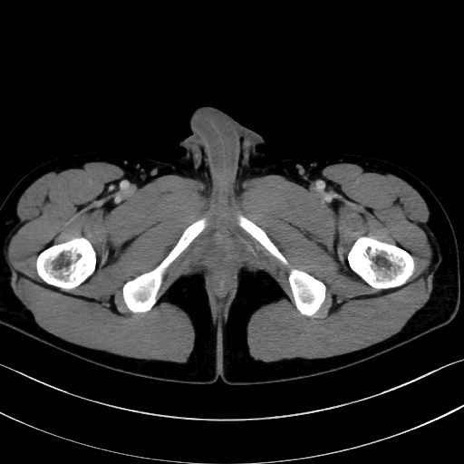

精嚢(seminal vesicle)のCT画像における解剖

症例

【症例】20歳代 男性 スクリーニング